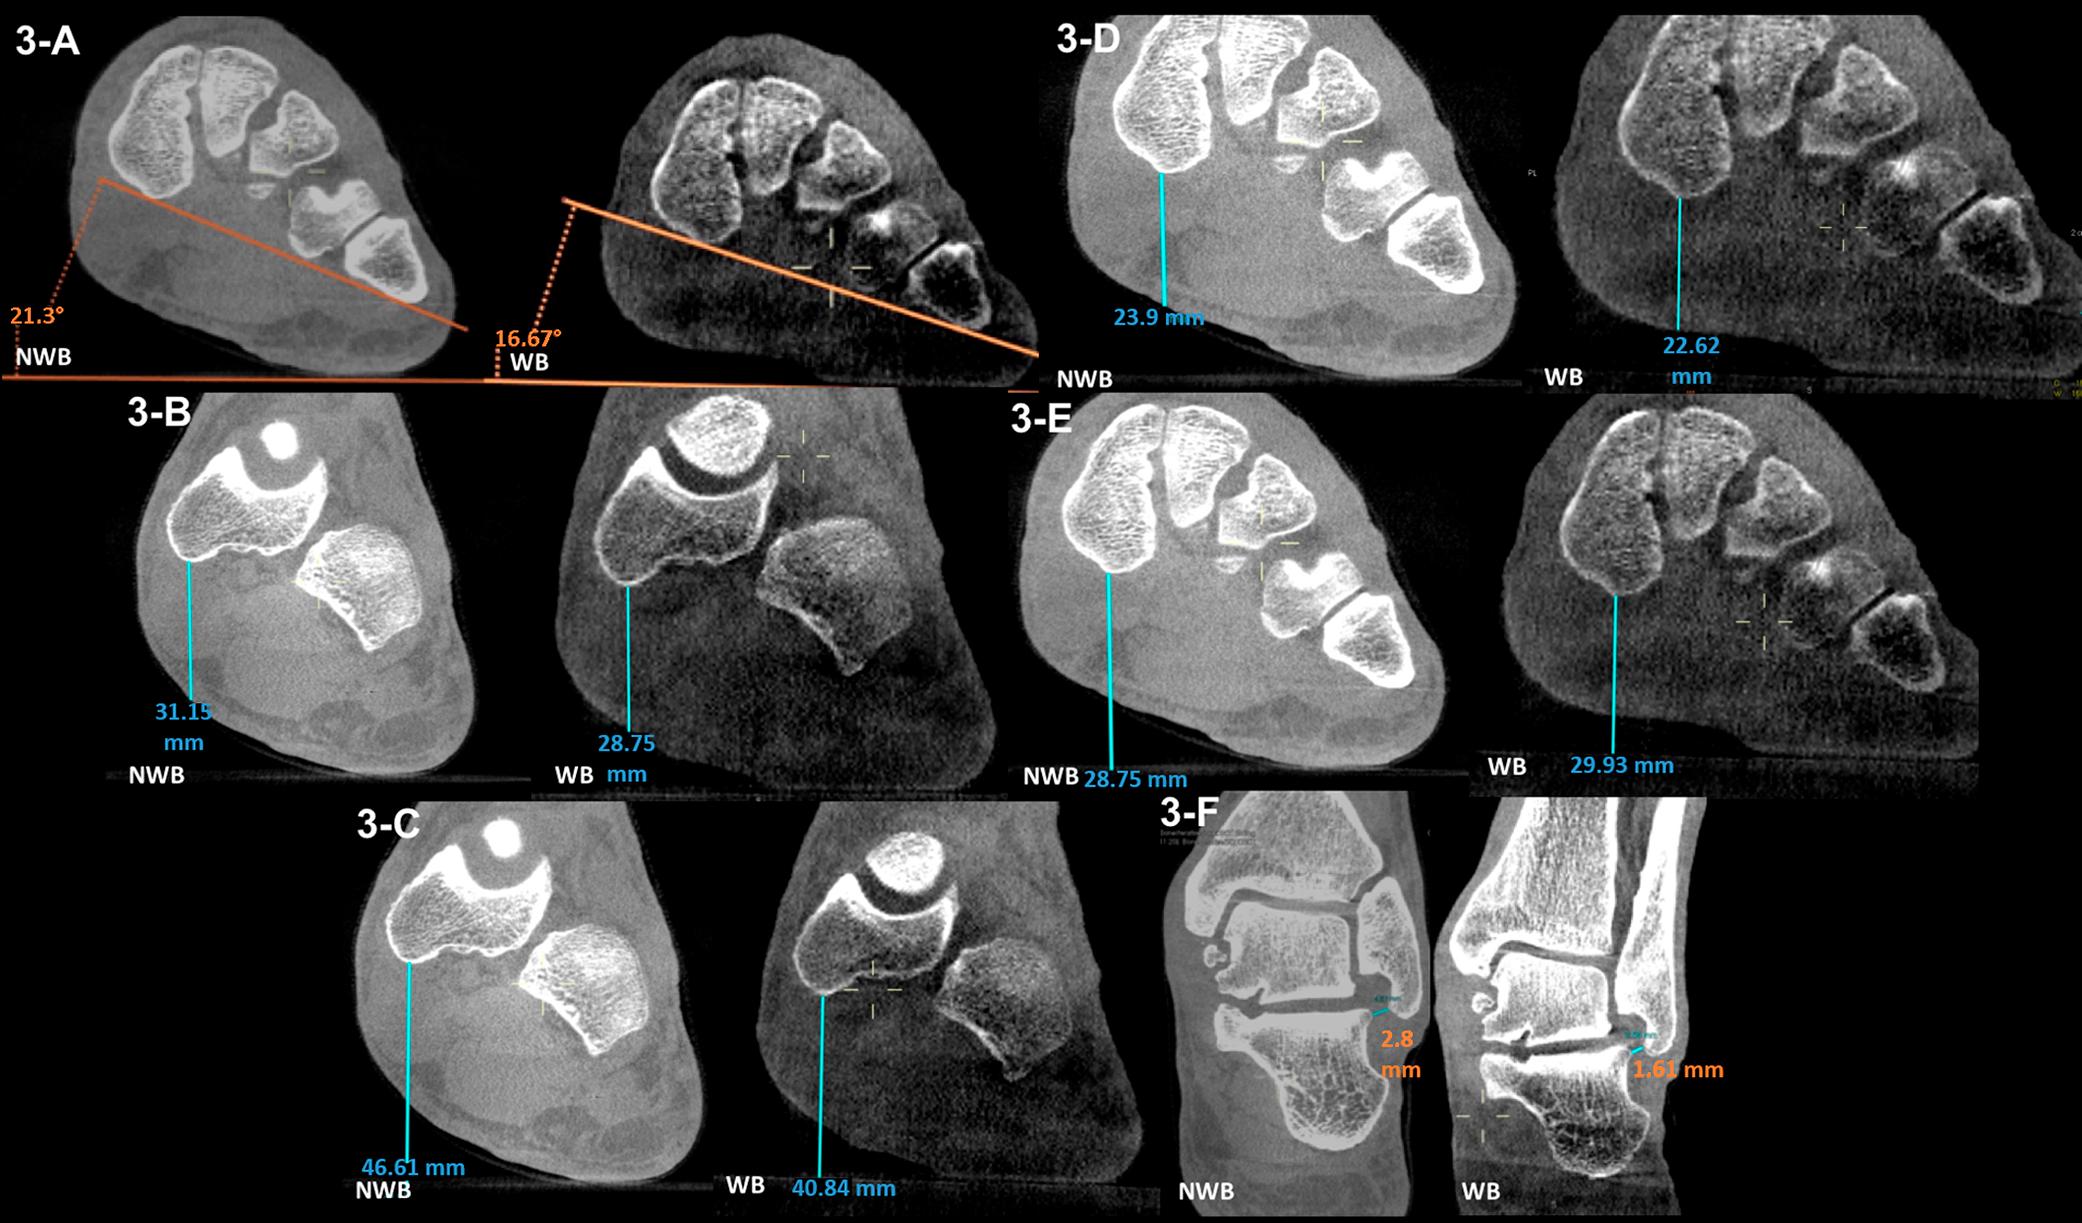

Does screw alignment affect tether breakage in vertebral body tethering? |  European Spine Journal | Springer Nature Link